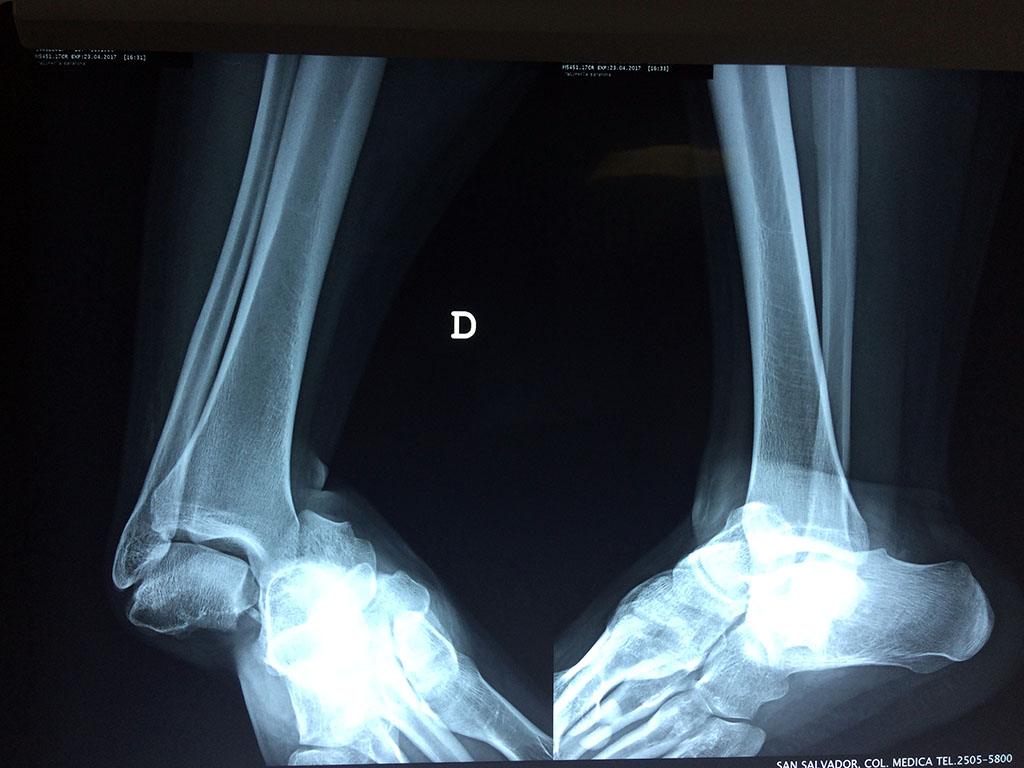

Una fractura de tobillo es la rotura de uno o más de los huesos del tobillo. Estas fracturas pueden ser:

- Parciales (el hueso está sólo parcialmente fisurado, no del todo).

- Completas (el hueso está perforado y está en 2 partes).

- Producirse en uno o ambos lados del tobillo.

Algunas fracturas de tobillo pueden requerir cirugía si:

- Los extremos de los huesos están desalineados entre sí (desplazados).

- La fractura se extiende hasta la articulación del tobillo (fractura intra-articular).

Cuando se necesita cirugía, es probable que esta implique el uso de clavijas de metal, tornillos o placas para sostener los huesos en su lugar mientras la fractura se consolida. Los elementos de soporte pueden ser temporales o permanentes.